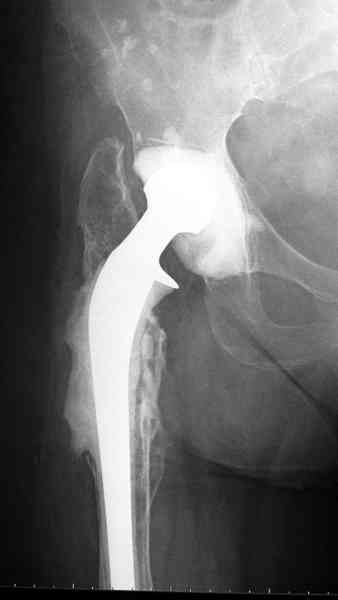

Приготовлен цемент из расчета: Tobramycin 2.4 g (2 флакона), Vancomycin 2 млн (4 флакона) и 2 упаковки цемента с добавлением дополнительного флакона цементной жидкости.

После обработки ацетабулярного компонента, ещё в мягком цементе в полости вертлужной впадины головкой бедренного компонента сделана выемка для головки, чтобы свежий цемент не прилипал к головке. Головку бедренного компонента завернул обычной стерильной фольгой, которую после образования выемки отлепил от головки.

Для спейсера в бедро использовал старый длинный бедренний компонент меньшего диаметра, облепленный со всех сторон цементом с антибиотиком.

Наглухо ушитая рана с дренажом зажила первично, после чего с больной потерял контакт, и только недавно, через 8 лет я осмотрел её. Она без проблем нагружает на конечность и передвигается с помощью трости. От окончательной операции по реконструкции отказывается, довольная результатом.

Имеются литературные данные, когда спейсер держали не более 6 месяцев, но этот случай бьет все рекорды, может быть для наших людей, обременных финансовыми трудностями, нужна другая шкала оценки сроков нахождения спейсеров.

и последние снимки.